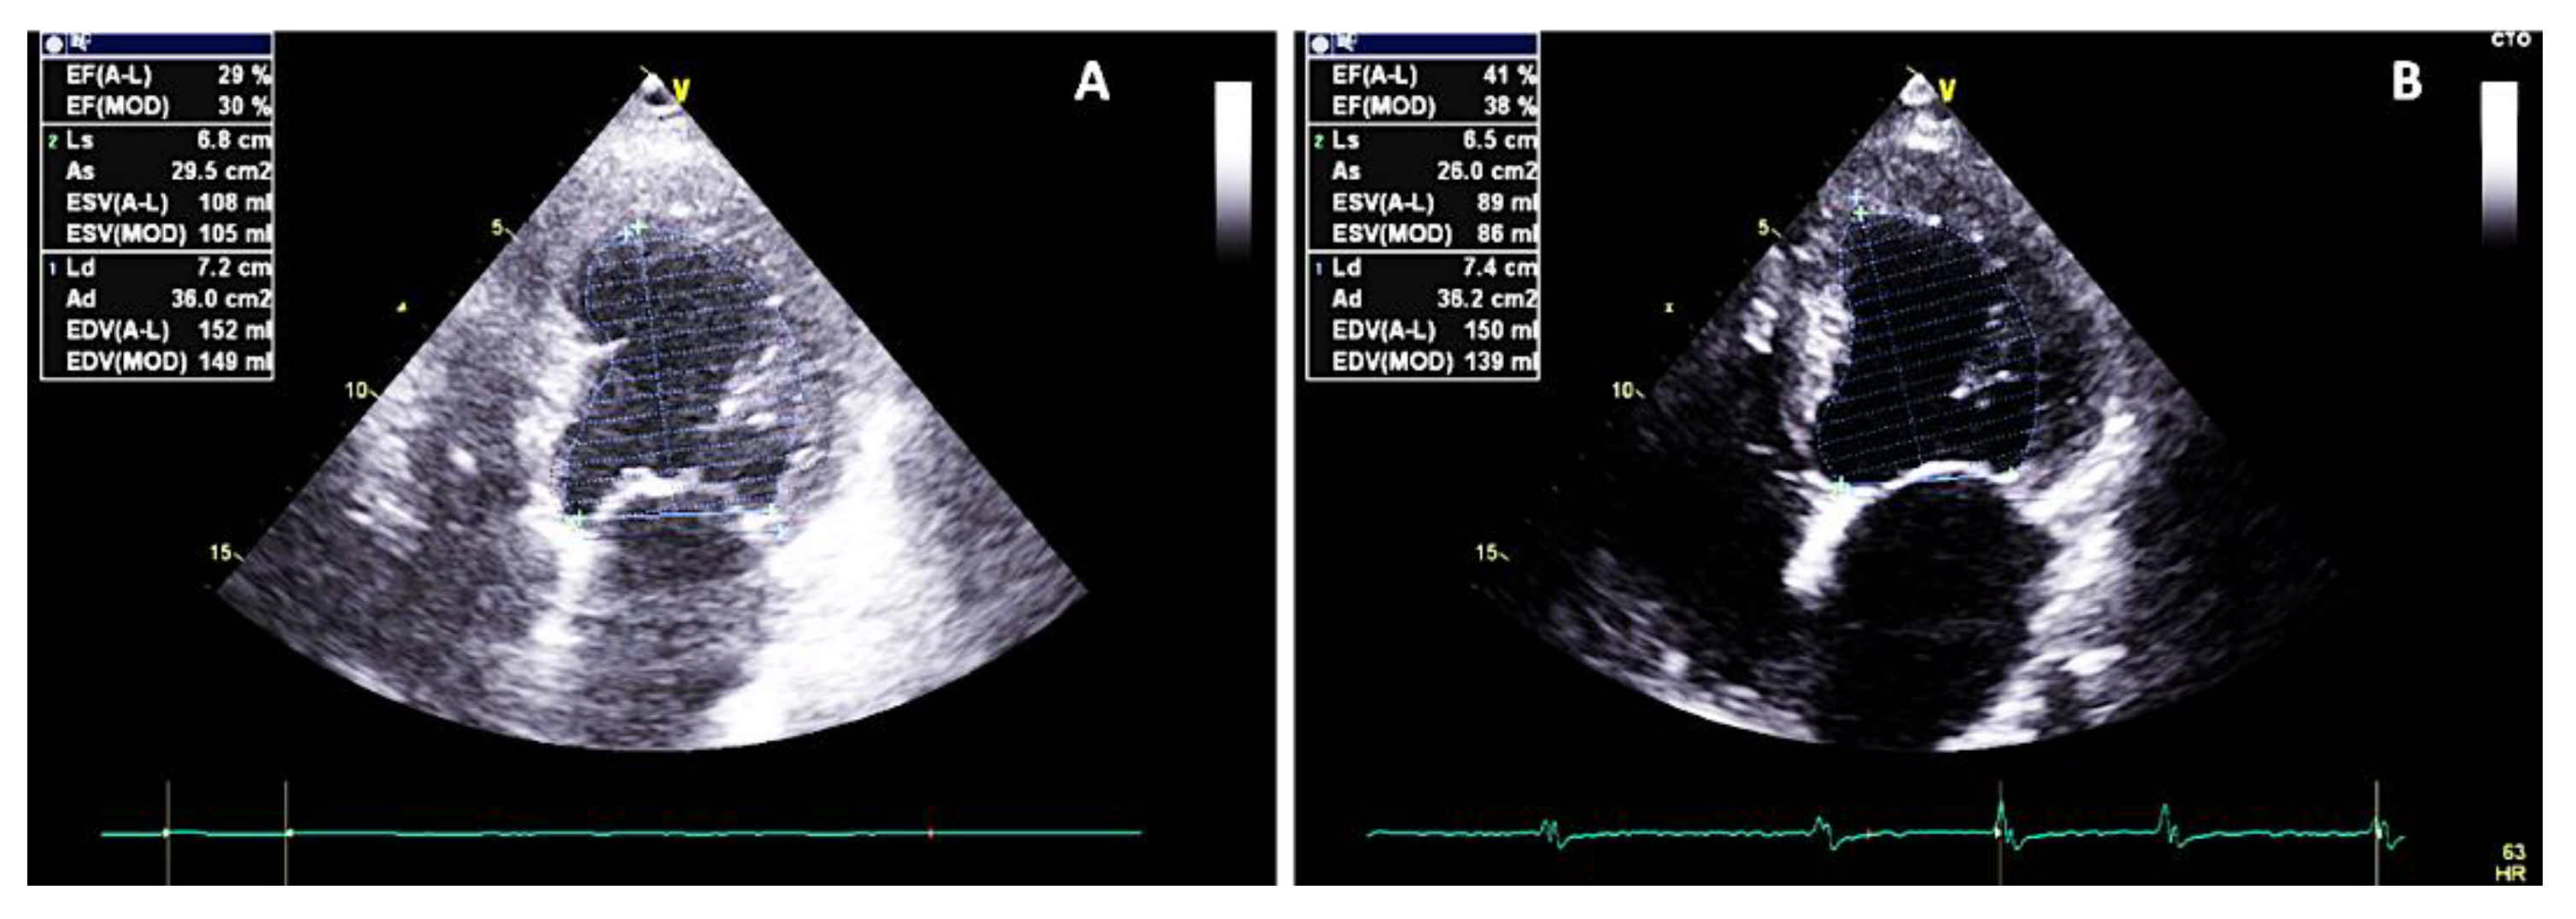

2. Case Report